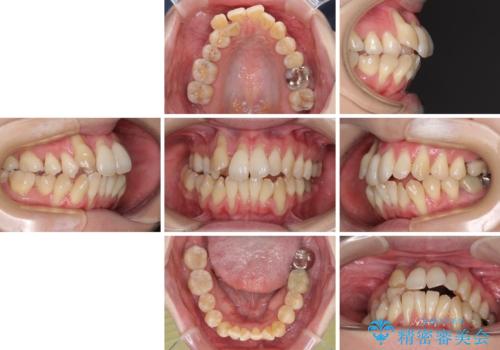

急速拡大装置 狭い骨幅を拡大した上で、顕著なデコボコを改善する抜歯矯正治療

- 前歯のデコボコと唇の閉じにくさを気にして来院された患者様です。

上顎骨よりも下顎骨の幅が広く、更には下顎骨が左側に変位していたため、より良い咬み合わせを達成することを目的として、急速拡大装置を用いて上顎骨を拡大することとしました。

デコボコが強い上に、口元の突出感も気にしていたため、上下左右の小臼歯4本を抜歯して、ワイヤー装置にて矯正治療を行うこととしました。